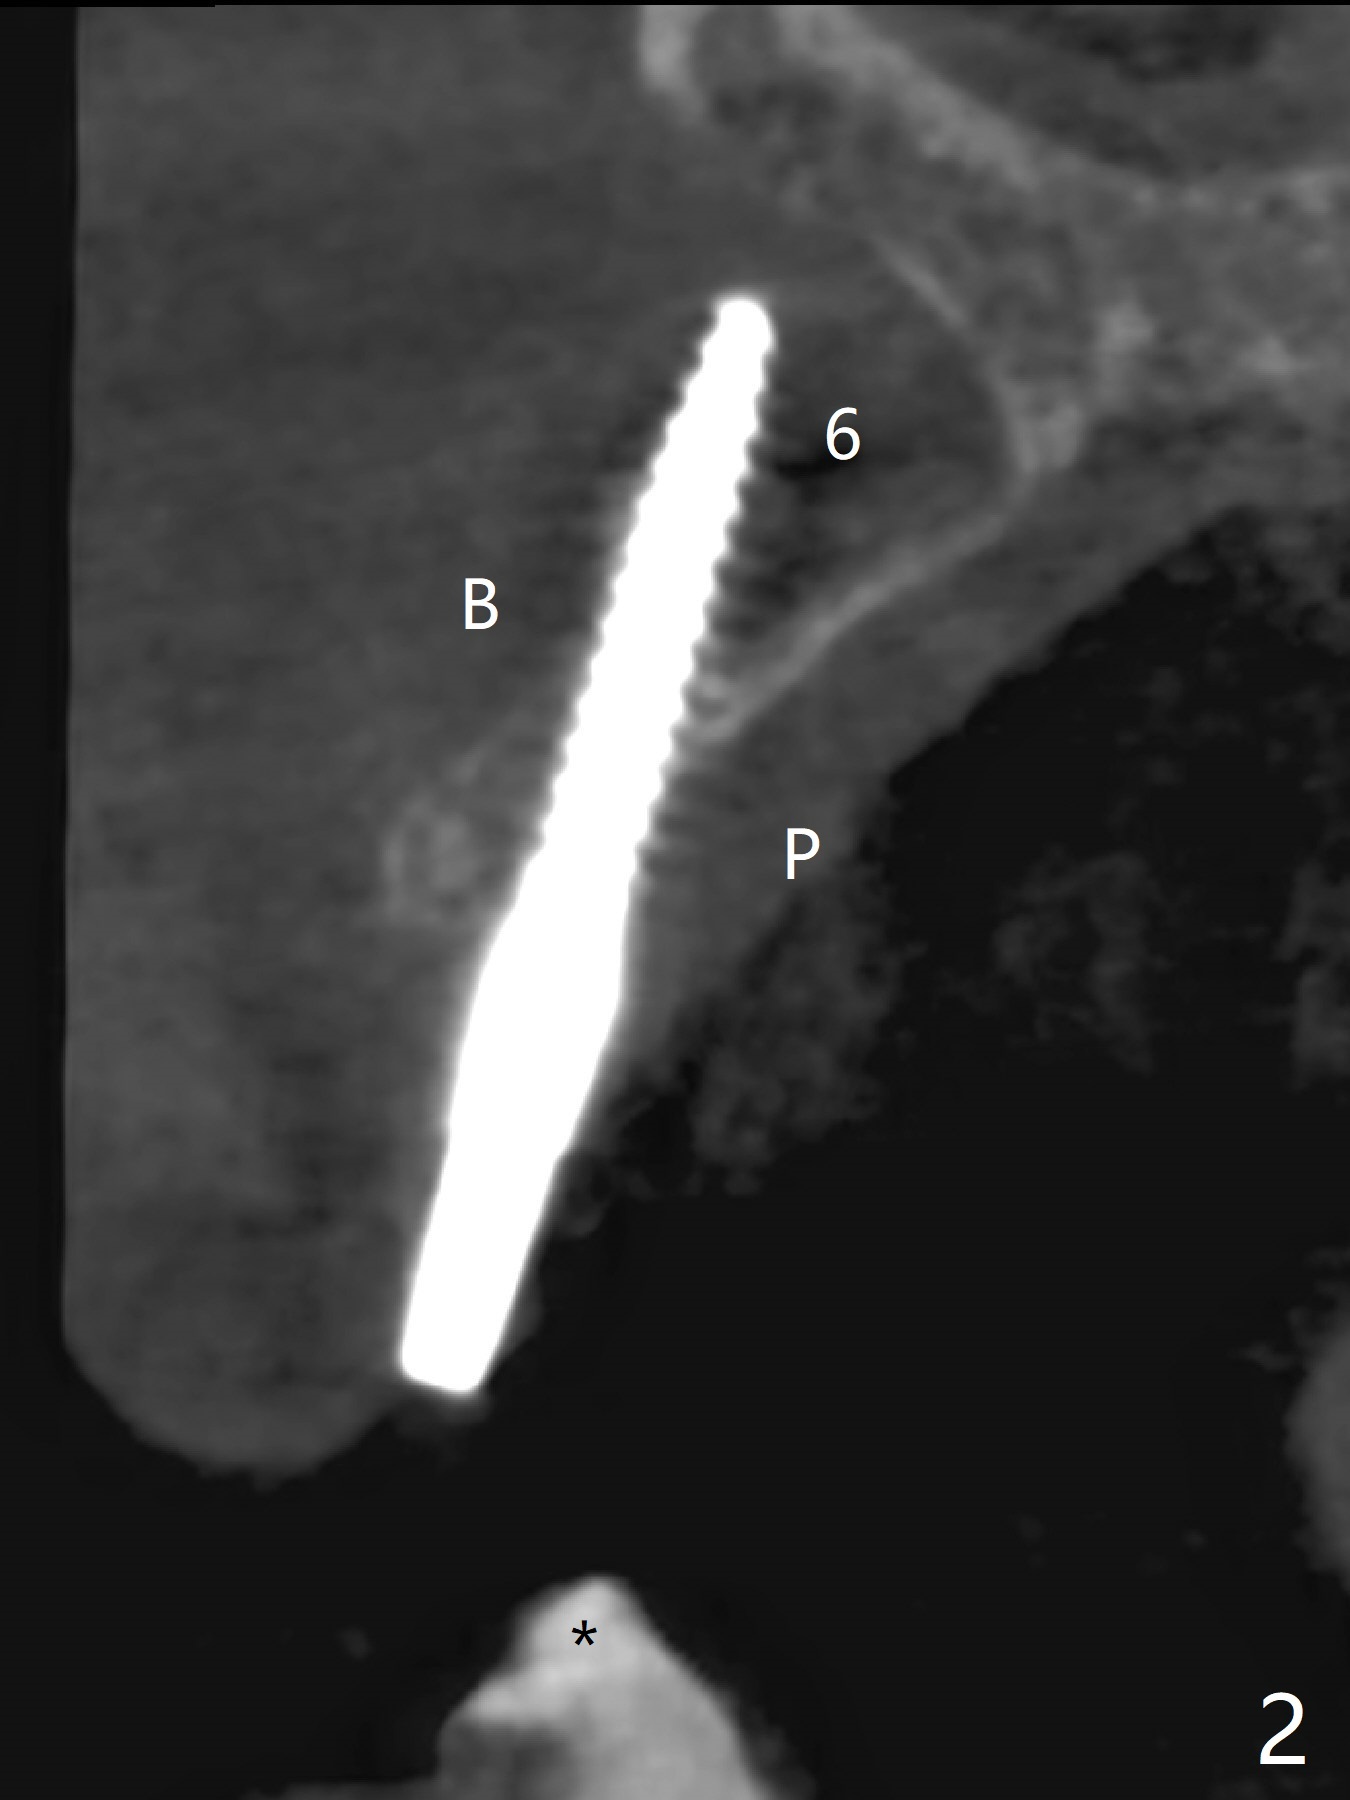

Osteotomy starts with guide and 2.2 mm drill for initial 3.5 mm palatal. A semilunar incision is made buccal to remove the impacted canine (#6 by sectioning). With direct vision buccal and palatal, the final osteotomy is finished free hand with 1.2 and 1.5 mm drills. Initially buccal perforation occurs, the osteotomy route is corrected later (Fig.1). When a 2.5x15 mm 1-piece implant is being placed, it perforates into the buccal concavity again. After redirection, the trajectory seems to be acceptable (Fig.2: CT coronal section). Three coronal implant threads are exposed partially palatal (Fig.3: CT 3-D palatal view). The implant is then turned 2-3 times with insertion torque reaching 40 Ncm. The incision is closed with suture following Osteogen plug placed in the most coronal portion of the socket (Fig.4 P) and allograft (*) in the remaining socket around the apical portion of the implant as well as palatal. The incision does not heal 1 month postop (Fig.5). PRF membrane will be placed next visit. Next visit the wound in fact is healing (Fig.6). PRF is unnecessary. The patient will return for impression 3 months postop. To be cosmetically pleasing, prepare local anesthetic and Laser for gingivectomy (Fig.7 red curved line). There is no bone loss around the implant 3.5 months postop (Fig.8). With topical, minor gingivectomy with laser creates papillae mesial and distal to the implant (Fig.9, 10 (incisal view)). After reline, there is appearance of a canine (Fig.11). The patient returns for impression 5 months postop; there is bone around the apex of the implant (Fig.12 *). The hard and soft tissues remain healthy when final restoration is delivered (Fig.13,14). The buccal plate reforms and #6 socket heals 12 months postop (6 months post cementation, Fig.15). The gingiva remains healthy at #4-6 nearly 2 years post cementation (Fig.16).